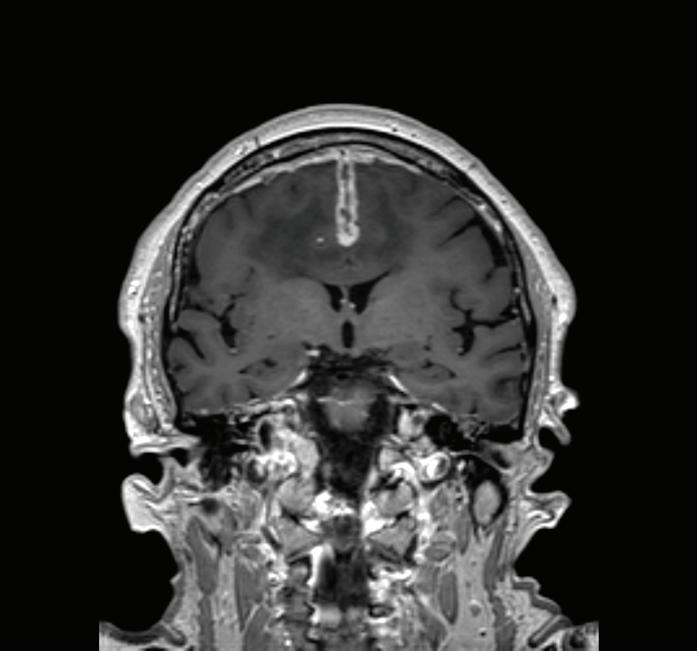

ПРЕДНА КЛИНОИДЕКТОМИЯ В. Наков

74 РЯДЪК